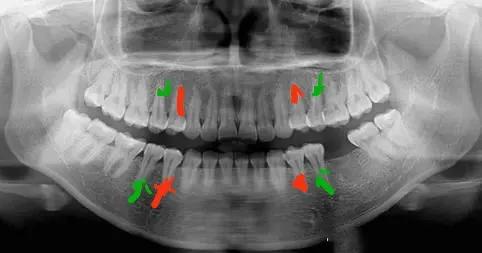

4號(hào)牙指第一前磨牙,又叫第一雙尖牙,是從門牙往后數(shù)的第四顆牙齒,在它后面的叫做第二前磨牙,稱為5號(hào)牙。正畸拔牙也是有一定規(guī)律的,通常情況下,第一前磨牙(4號(hào)牙)是拔牙矯正中_常拔除的對(duì)象。

當(dāng)牙列擁擠程度或牙弓前突相對(duì)小時(shí),會(huì)選擇拔第二前磨牙(5號(hào)牙),前磨牙的咀嚼效率低,影響_小,拔除前磨牙不容易引起患者面型坍塌和美觀。當(dāng)然也有其他情況的存在,需要根據(jù)患者情況具體判斷。

另外,正畸拔牙大部分是左右對(duì)稱拔除,可防止中線偏移,保證美觀與咬合關(guān)系正常。

紅色為4號(hào)牙,綠色為5號(hào)牙